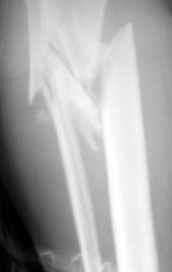

Больная поступила 11 12 2004 с открытым оскольчатым переломом в/3 обеих костей правой голени со смещением после автодорожной аварии. (1Б по Каплану, тип 2-классификация Gustilo-Anderson).

Наложено скелетное вытяжение . обработана рана, наложены швы, заживление идет благоприятно. На контрольных рентгенограммах стояние отломков несколько улучшилось. Рис 1,2 Обдумываем в коллективе несколько вариантов возможного лечения:

Рентгенограмма при поступлении. Думаю на ней видно распространение линии перелома вниз